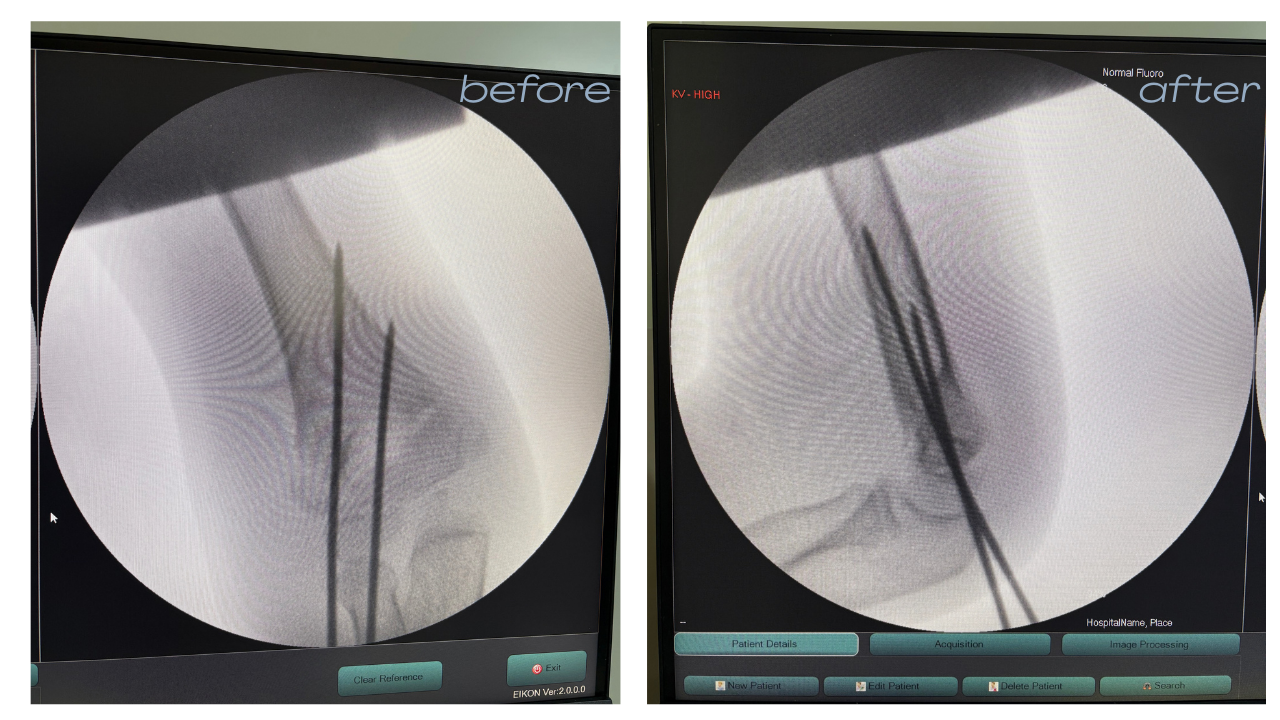

Sports Medicine & Injury Treatment (Arthroscopy)

Specialized treatment for ligament tears and sports injuries using minimally invasive "keyhole" surgery. Our integrated rehab programs help athletes and active individuals return to peak performance safely.